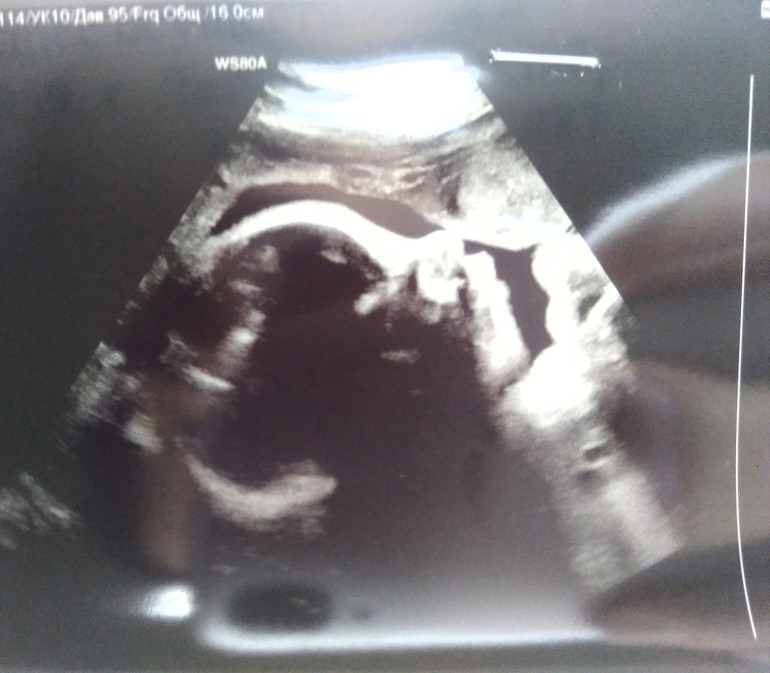

Вчера прошли,думаю завершающее УЗИ в эту беременность! Срок поставили 37,2 - предполагаемый вес 3.080 (+/-), кровотоки все в норме, плацента второй степени зрелости... Вообще время пролетело незаметно, на 20.07 дали направление на госпитализацию в перинатальный центр (даже не верится), не хочу конечно ложится заранее,ибо пдр только 25.07, но так как предстоит ПКС, всё же съезжу на консультацию... Доделываем ремонт в квартире, купили коляску, одежду на первые два месяца. Интересно сколько будет вес при рождении нашего сыночка) Девчонки, как у вас самочувствие? Всё ли куплено для малыша? У кого предстоит ПКС что нужно с собой в роддом?

Сегодня был пройден третий скрининг! Матвейка решил разместиться как положено (головкой вниз), что не может не радовать! Весим почти 1860кг,что тоже считается нормой! Так что все хорошо, растём и развиваемся в срок))) ну и фото на память)

Срок 13+3, всё соответствует сроку!

Ктр - 81мм

Твп - 2мм

Предполагаемый вес плода - 90гр

По крови риски низкие. Скажите, может кто не давно проходил, у кого сколько весит малыш?